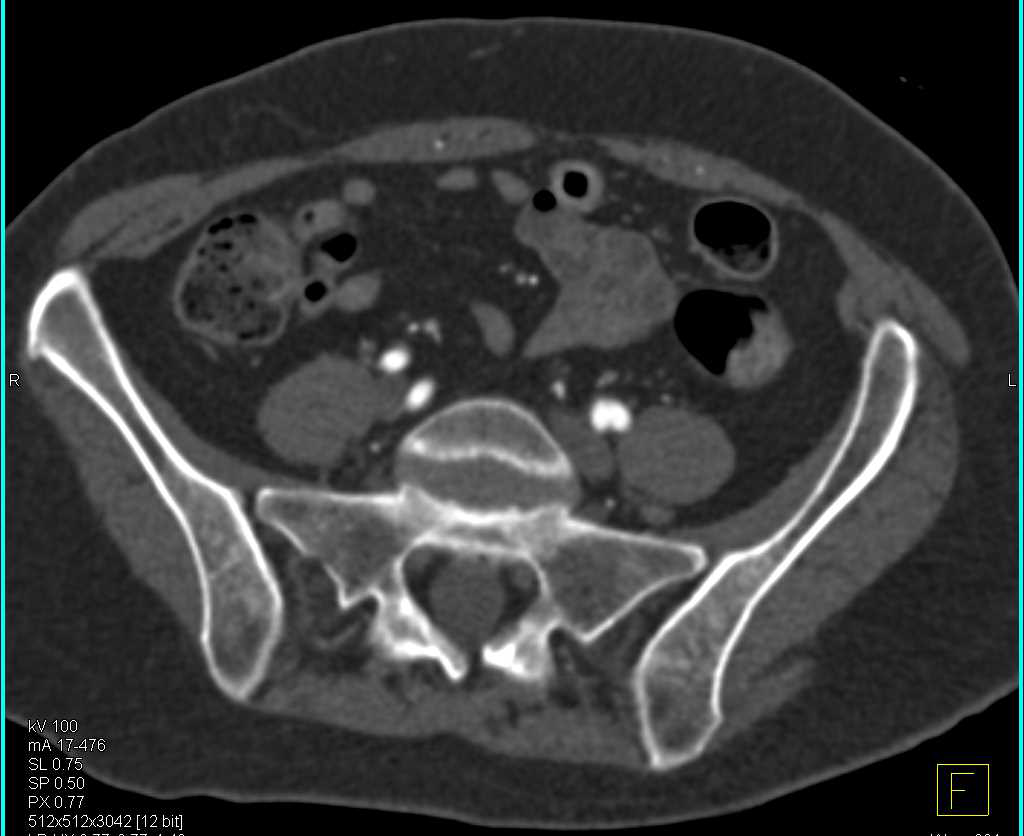

Vascular Mapping of the Pelvis and Upper Thigh